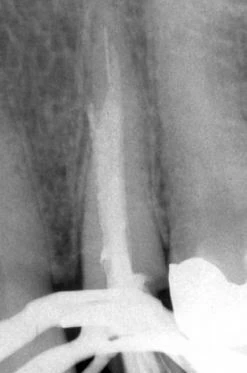

Hình 6. A, Trâm H có đường kính nhỏ xuyên qua chóp của răng nanh hàm trên bị gãy ở đoạn 1/3 cổ ống tủy. B, Mảnh dụng cụ được tháo ra bằng một kìm Masserann, và hình ảnh chi tiết của cơ chế khóa. Lưu ý: trâm nikel-titanium (NiTi) không thể bị uống bằng cách này. Lực khóa của kìm lên dụng cụ nikel-titanium hầu như rất yếu. C, Hoàn tất việc điều trị lại.

Hình 6 cho thấy một trường hợp thất bại trong đó một trâm H cỡ nhỏ bị bỏ lại ở 1/3 cổ ống tủy và kéo dài quá chóp gần 2 mm. Phần còn lại của ống tủy được trám bít bằng gutta percha. Việc lấy mảnh dụng cụ được hoàn thành bởi một kìm IRS sau khi loại bỏ phần gutta percha phía trên bằng đầu siêu âm. – Việc lấy mảnh dụng cụ gãy ở đoạn từ 1/3 cổ đến 1/3 giữa cần những kỹ thuật làm hợp lý, đáng tin cậy và hiệu quả. Như đã lưu ý ở trước, dụng cụ NiTi được sử dụng phổ biến bây giờ có khuynh hướng dễ gãy trong ống tủy hơn các dụng cụ bằng thép không gỉ truyền thống trước đây. Thật đáng tiếc rằng đặc tính dễ gãy thường là do việc sử dụng dụng cụ sai và không phù hợp chứ không phải là khuyết điểm của chính dụng cụ. Tuy nhiên, do hiệu quả hạn chế của dụng cụ siêu âm đối với kim loại Nickel-Titanium nên kỹ thuật loại bỏ nó tương đối khác. Với thép không gỉ, rung siêu âm có thể được sử dụng để tạo rãnh xung quanh cấu trúc răng và rung trực tiếp lên kim loại. – Ngược lại, việc rung kéo dài trên trâm NiTi thường sẽ dẫn đến làm gãy vùng chiều dài lộ ra của dụng cụ. Nếu rung siêu âm được cân nhắc, nó nên được sử dụng với mục đích chính cho việc đào xung quanh hoặc song song với mảnh gãy, tránh tình trạng tiếp xúc liên tục với mảnh dụng cụ. Nếu thiết bị siêu âm được sử dụng với mục đích làm cho mảnh gãy lỏng ra, mảnh gãy nên được tách rời ra khỏi ngà xung quanh để tăng khả năng tháo ra được. Cùng lúc, thiết bị siêu âm nên được sử dụng ở mức cài đặt năng lượng thấp và chỉ sử dụng trong một khoảng thời gian ngắn. – Nếu một mảnh dụng cụ thép không gỉ ở ½ trên ống tủy, sử dụng Masserann hoặc kìm IRS không có hạn chế nào ngoài việc nó đắt và không có tính linh hoạt như một dụng cụ siêu âm. Vì vậy, hầu hết các nhà lâm sàng sẽ lựa chọn một số loại dụng cụ siêu âm. Lợi ích của thiết bị kìm là cơ chế khóa. Với một rãnh nhỏ rất hiệu quả, làm bằng thép không gỉ, nó có thể tạo một lực kìm chặt đáng kể. Tuy nhiên, cần cẩn thận khi khóa vào phần đoạn trâm vì có thể xảy ra việc gãy phần trâm lộ ra. Lưu ý là cơ chế khóa được minh họa ở hình 6.B. – Xét về mặt tích cực, trâm tay NiTi thường gãy đoạn ngắn hơn loại trâm bằng thép không gỉ và do nó được thiết kế những rãnh khác nhau nên không bị khóa chặt vào trong cấu trúc răng. Lực rung nhẹ từ một thiết bị siêu âm hoặc việc xoay nhẹ kìm Masserann cũng giúp làm lỏng trâm NiTi. Nếu đuôi của mảnh dụng cụ gãy gần miệng ống tủy, thiết bị siêu âm sẽ giúp tháo nó ra nhanh chóng; hoặc một mũi khoan trephine có thể giúp tạo khoảng trống cho kìm hoặc forcep đưa vào. Nếu dụng cụ là thép không gỉ thì khi sử dụng mũi khoan trephine, mảnh dụng cụ không bị gãy hoặc bị làm yếu đi. Thủ thuật cũng giống như việc tháo cây mang gutta percha có lõi bằng kim loại hoặc côn bạc được cắt ở tại vị trí miệng ống tủy. Đặc trưng của mũi khoan trephine là nó sẽ men theo dụng cụ dễ dàng dù cho mảnh dụng cụ bằng thép không rỉ hay NiTi. Một khi cán dụng cụ được bộc lộ ít nhất 2 mm thì lúc đó có thể thận trọng dùng kìm gắp ra. Loại kìm 1.2-mm cũng đã thích hợp cho các dụng cụ kích cỡ lớn như trâm số 40. Do dụng cụ nội nha có hình dạng xoắn ốc, sau khi bắt kìm ta sử dụng một lực vặn nhẹ ngược chiều kim đồng hồ để rút dụng cụ ra. – Các tác giả trước cũng đã mô tả nhiều về việc tháo mảnh dụng cụ sâu trong ống tủy bằng cách xuyên qua bằng mũi Maserann. Tuy nhiên, trên thực hành lâm sàng, việc khoan vào 1/3 chóp chân răng là cực kỳ mạo hiểm và không được khuyến khích làm kể cả khi chân răng thẳng và rộng đủ cho mũi GG lớn có thể mở rộng lối vào ở phần trên ống tủy. Trong hầu hết các nỗ lực nhằm lấy mảnh gãy, mũi trephine sẽ dẫn đến đục thủng thành bên ống tủy do giải phẫu ống tủy có khuynh hướng thuôn về phía chóp. Hình 7 cung cấp dữ liệu một trường hợp thất bại khi lấy mảnh dụng cụ nằm ở 1/3 chóp. Mặc dù ống tủy được làm rộng ở phần cổ bằng mũi GG trước khi áp dụng kỹ thuật Masserann, mũi trephine vẫn không thể đi đến được vị trí mảnh gãy. Hơn nữa, mũi trephine gần như gây xuyên thủng ở thành bên.